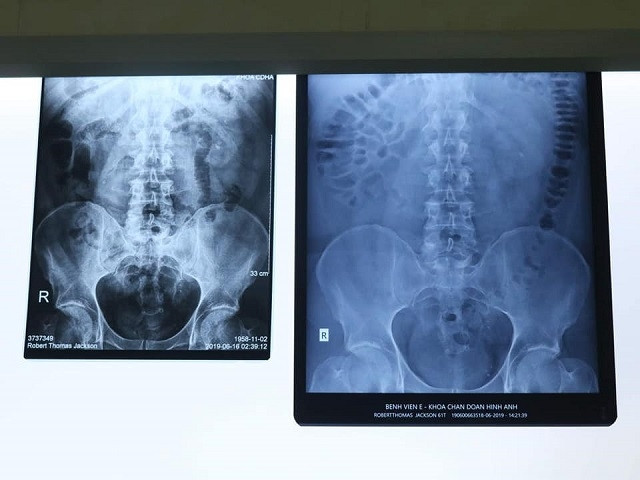

Phim chụp X-quang sỏi niệu quản của bệnh nhân.

Chiều ngày 18-6, bệnh nhân được đưa vào cấp cứu tại Bệnh viện E trong tình trạng đau dữ dội vùng bụng dưới và không thể đi lại được. Bệnh nhân ngay lập tức được làm xét nghiệm, chụp X-quang. Kết quả cho thấy, bệnh nhân bị sỏi niệu quản ở vị trí 1/3 trên, bên phải.